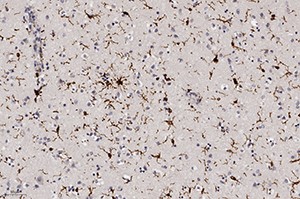

Окраска на микроглию при ИГХ (Iba-1) показала их активацию, что свидетельствовало об иммунном ответе ткани мозга на данную инфекцию, а также активацию периваскулярных астроцитов (ИГХ к КГФБ) (см. рис. 8).